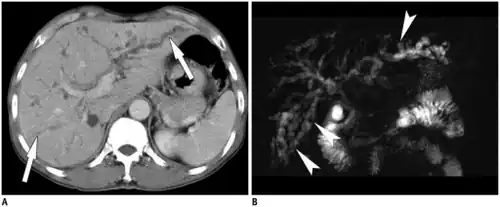

a,b)Pyogenic cholangitis with Clonorchis sinensis infestation in a male individual

Dwelling in the bile ducts, C. sinensis induces an inflammatory reaction, epithelial hyperplasia, and sometimes even cholangiocarcinoma, the incidence of which is raised in fluke-infested areas.[25]

Typical imaging features center around imaging of the liver with CT, ultrasound, or MRI for detection of primary biliary cirrhosis. Traits that raise suspicion for the infection include intra- and extrahepatic dilatation and structures with intraductal pigmented stones, usually in the absence of gallstones and with regions of segmental liver atrophy, particularly the lateral aspect of the left hepatic lobe. Also, reduced arborization of peripheral ducts is seen. A full 5% of chronic infections go on to develop cholangiocarcinoma.[28]